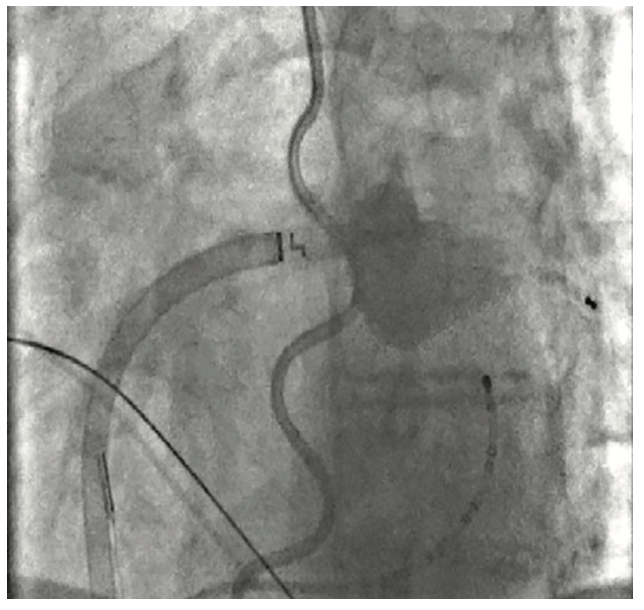

The HeartLight X3 System (CardioFocus) is a visually guided laser balloon technology for the treatment of symptomatic drug-refractory paroxysmal atrial fibrillation (AF). It consists of an ultra-compliant balloon, a motor-controlled laser energy source, and a 2 French camera for direct visualization of the pulmonary vein, making it ideal for pulmonary vein isolation (PVI). The HeartLight X3 System is developed and manufactured by CardioFocus, Inc, in Marlborough, Massachusetts. More than 14,000 patients have been treated worldwide. In this feature interview, EP Lab Digest speaks with Drs Celso Acevedo and Nguyen Phan about their experience with the HeartLight X3 System. Dr Acevedo is with Florida Heart and Lung in Ocala, Florida. Dr Phan is with the Ascension Medical Group in Milwaukee, Wisconsin.

What I like about the HeartLight X3 system is that it combines that flexibility of being able to treat different veins with direct visualization of tissue contact and lesion placement. The platform is a compliant balloon that will accommodate different vein sizes, anywhere from 7-41 mm, as well as an endoscope that allows the operator to look directly inside the PV, so no assumptions have to be made. When you use a mapping system, you are using data that was taken at the beginning of the case and making assumptions during mid to late case. The HeartLight Laser Balloon is fixed to the PV so there is no guesswork—it takes away that uncertainty.

Phan: It makes the procedure a lot simpler. We are able to quickly cannulate the vein and isolate with the laser balloon to directly visualize where we are ablating. We no longer need three-dimensional mapping to tell us where we are—we can see the vein and know exactly where to ablate. This significantly cuts down on time, as we are able to do cases in half the time that it previously took us. So those are the 2 key features that have made the biggest impact—we are able to ablate much faster and the procedure is safer because we can see exactly where we are going.